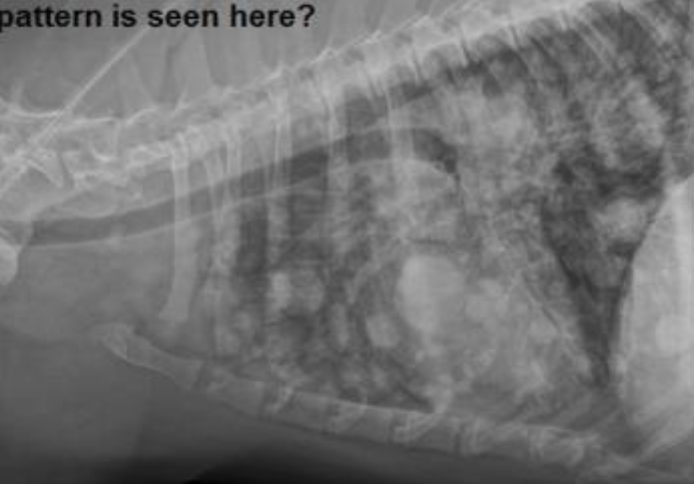

Cat. Likely condition? How do you know?

Feline asthma

flat diaphragm, donuts (bronchial pattern), huge lungs